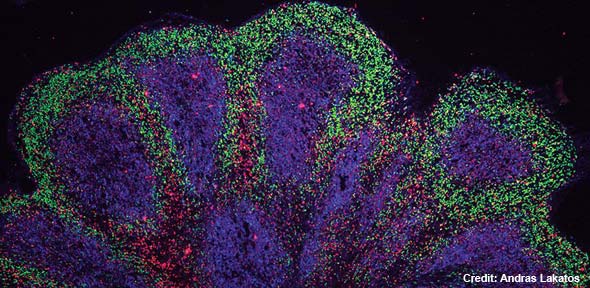

стволовые клетки

биоинженерия